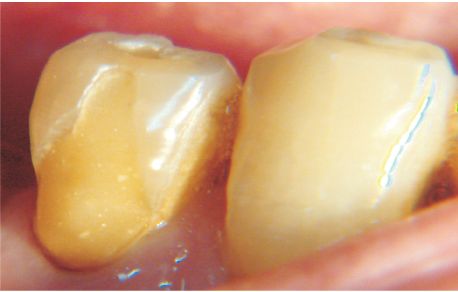

2. Redondeadas, cóncavas o en cuchara, ubicadas en el 1/3 cervical y avanzan hacia los tejidos radiculares (fig. 2).

3. Angulares o en cuña, ubicadas a nivel del Límite Amelo Cementario (LAC), (fig. 3).

Fig. 2 Lesión cóncava en forma de cuchara.

Asociada clásicamente a abrasión

Fig. 3. Lesión en cuña, angulada. Etiología controversial

Fig. 4. Lesión atípica, idiopática. Muy difícil de

explicar por cargas oclusales y cambios de fulcrum